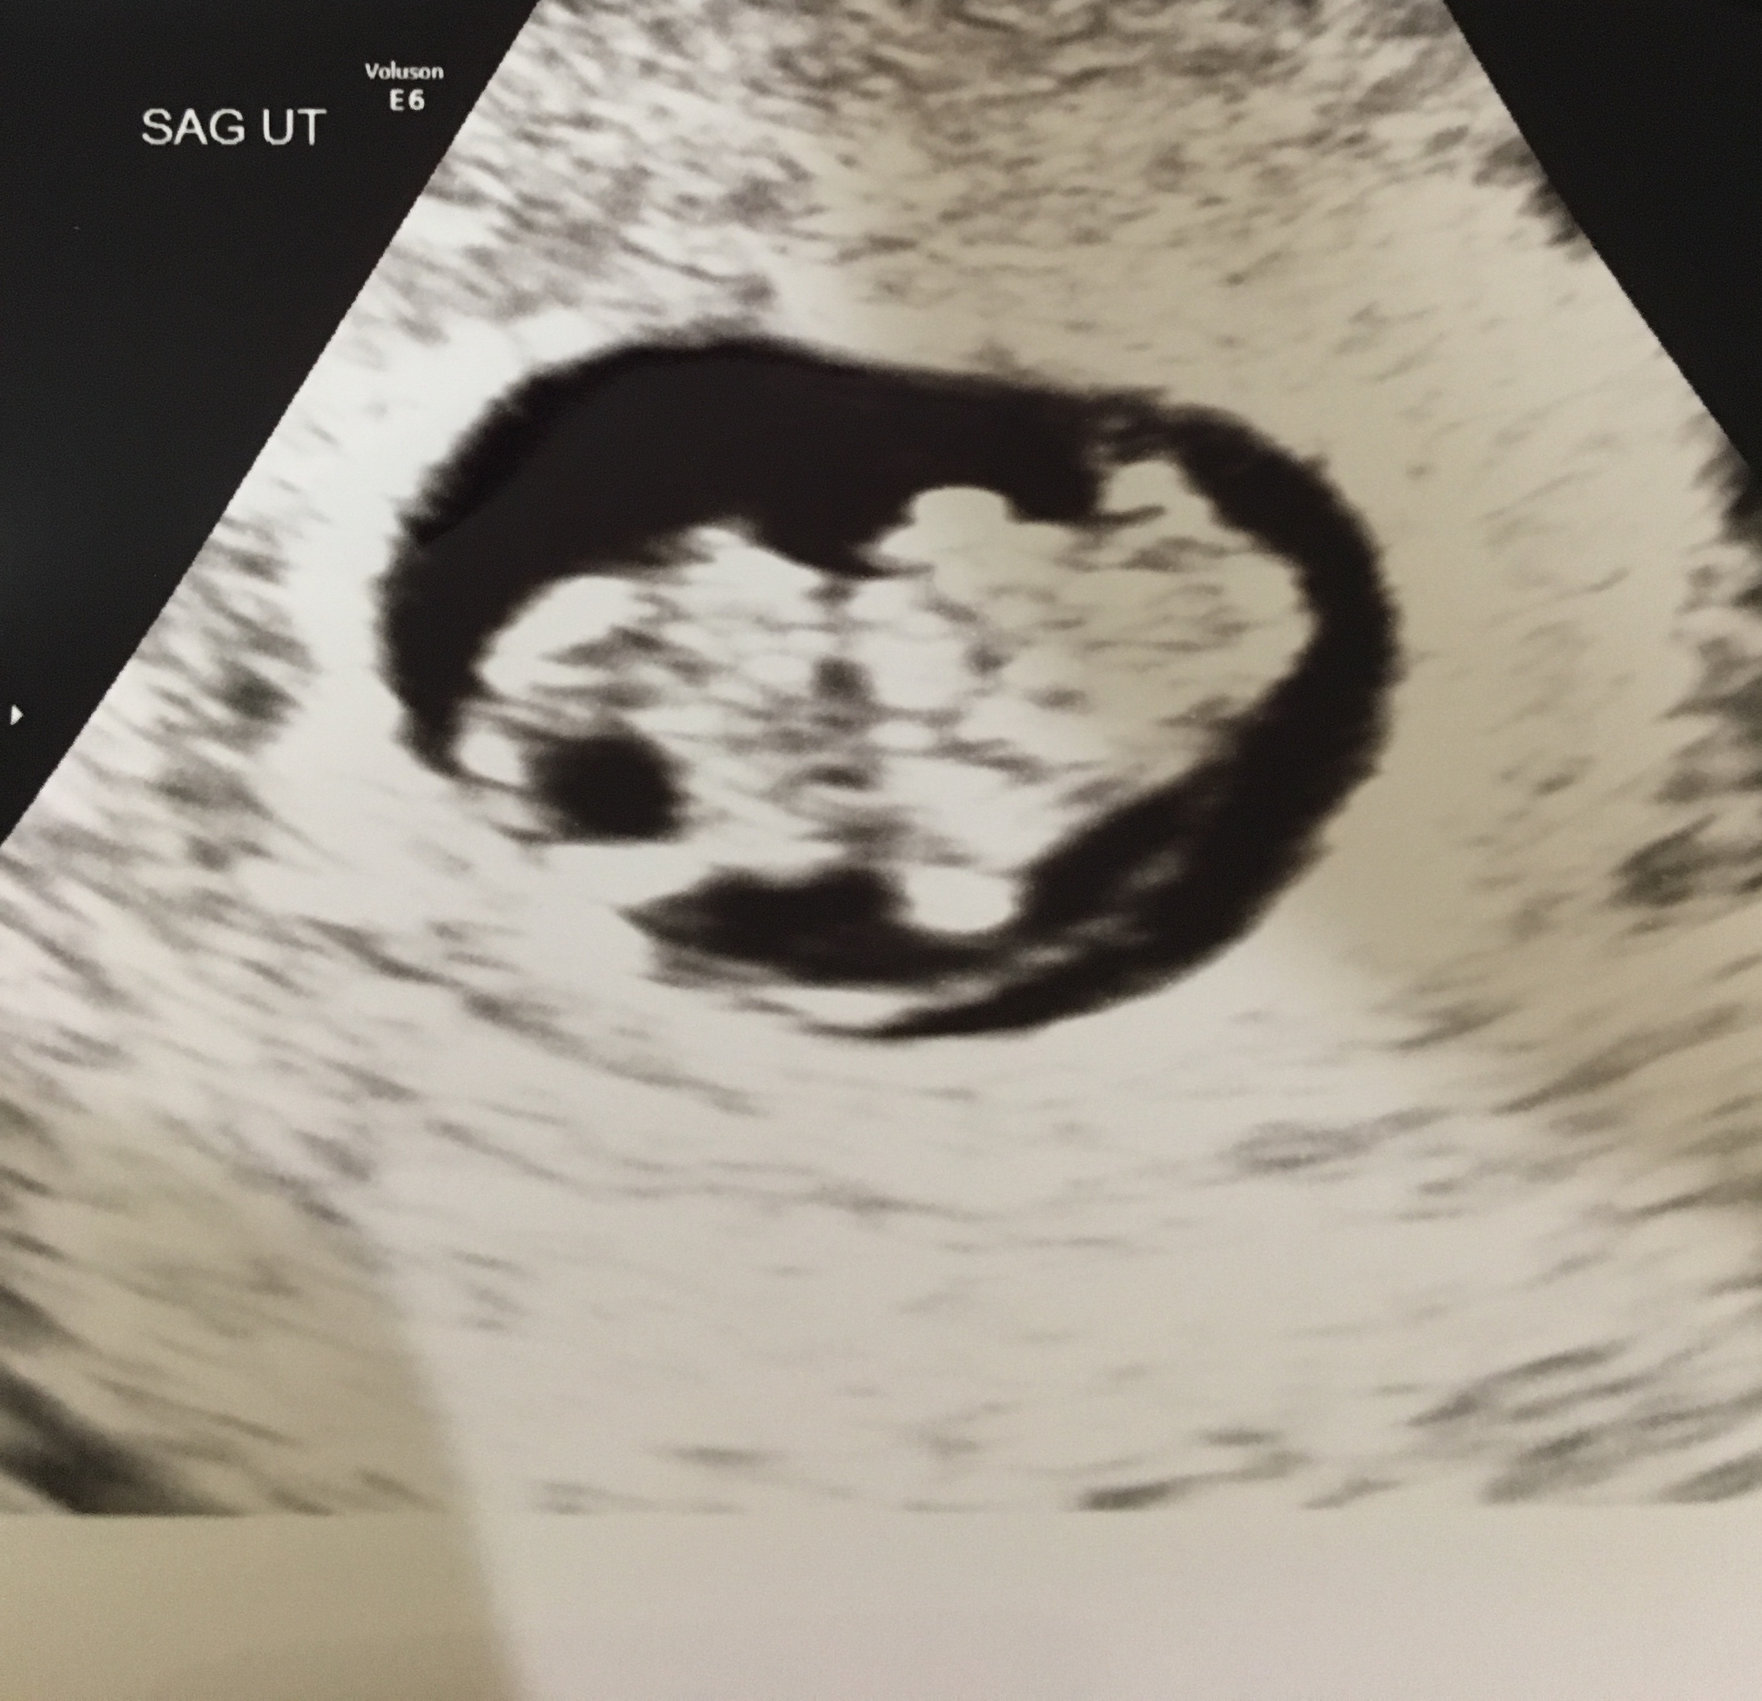

Measuring exactly what we thought it should be (7 weeks 6 days) and heartrate of 157 bpm. Definitely cried some happy tears seeing our little gummy bear. ❤ With my first pregnancy I MCd before we even got an ultrasound, so this was really my first experience seeing a baby on the monitor.